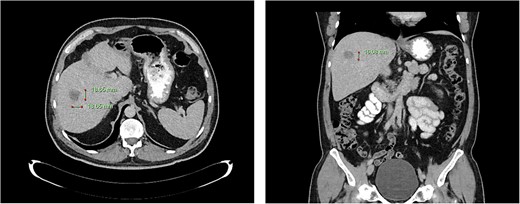

Computed tomography dated 12 March 2013 of the abdomen and pelvis measuring 8.70 mm (anterior–posterior) lesion at liver segment 5/6 in axial (left) and coronal (right) view.